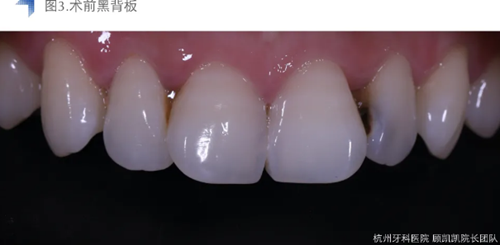

考慮到術(shù)前口內(nèi)檢查及影像學(xué)檢查提示齲損較近髓,與患者溝通可能設(shè)計牙髓治療??紤]到美學(xué)及長期穩(wěn)定考量,與患者溝通直接樹脂充填與間接瓷貼面修復(fù)兩種修復(fù)方式,患者考慮后決定采用間接椅旁瓷貼面修復(fù)。